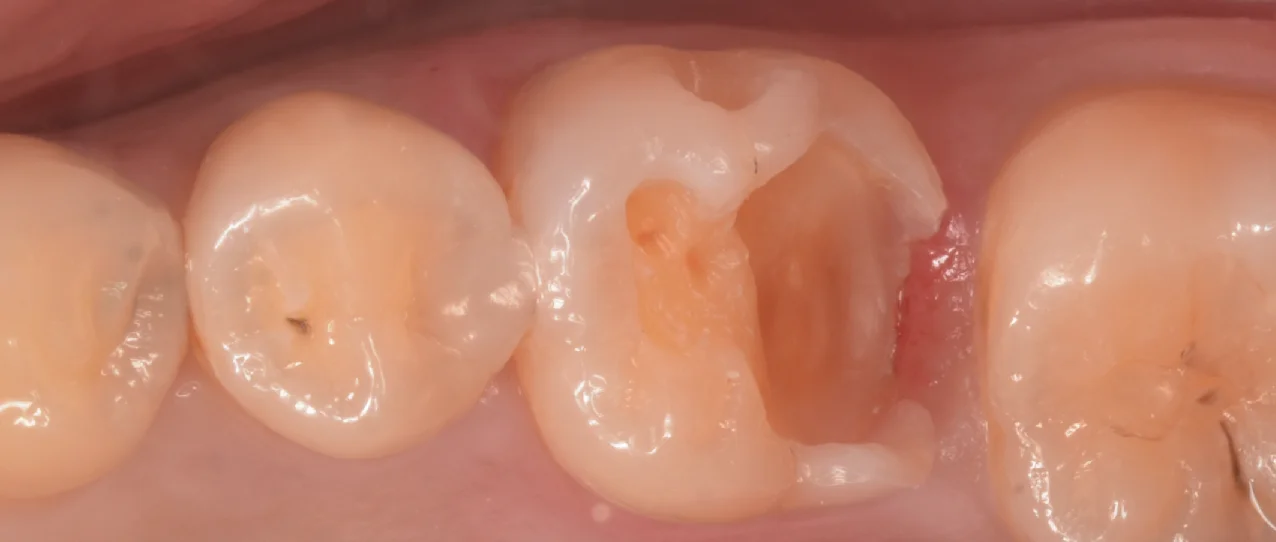

詰め終わった写真がこちらになります。

歯科医師の方のCAD/CAMインレーを治療。|坂寄歯科医院(取手市藤代) - 画像4

噛み合わせの部分がすでにCAD/CAMインレーに置き換わっていたため、流石に噛み合わせの調整は結構することになりましたね・・・。

歯とのギャップもなく適切な形態も付与できているので今までより歯が少なくなってはいますが、今までよりも長期予後は期待できるはずですよ。